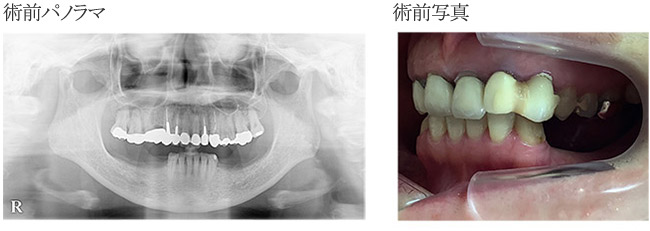

з—ҮдҫӢ4

дёҠйЎҺе·ҰеҒҙ1з•ӘгҒ®еүҚжӯҜз ҙжҠҳгҒ«гҒЁгӮӮгҒӘгҒҶж¬ жҗҚиЈңз¶ҙ

жӯҜгҒ®з ҙжҠҳгҒ®гҒҹгӮҒгӮӨгғігғ—гғ©гғігғҲеҮҰзҪ®гӮ’гҒ”еёҢжңӣгҖӮ

| в‘ жІ»зҷӮеҗҚ | дёҠйЎҺеҸіеҒҙпј‘з•ӘгҒ®з ҙжҠҳгҒ®гҒҹгӮҒгӮӨгғігғ—гғ©гғігғҲеҮҰзҪ®гҒ«гӮҲгӮӢжӯҜеҶ дҝ®еҫ©гӮ’гҒ”еёҢжңӣгҒ•гӮҢгҒҰжқҘйҷў |

|---|---|

| в‘ЎиІ»з”Ё | гӮёгғ«гӮігғӢгӮўгҒ«гӮҲгӮӢжӯҜеҶ дҝ®еҫ©пјҲгӮөгғјгӮёгӮ«гғ«гӮ¬гӮӨгғүдҪҝз”Ёпјү35дёҮеҶҶ |

| в‘ўжӮЈиҖ… | пј•пј–жӯігҖҖеҘіжҖ§ |

| в‘ЈжІ»зҷӮеҶ…е®№ | дёҠйЎҺеҸіеҒҙпј‘з•ӘгҒ«гҒҜеүҚиЈ…еҶ гҒҢиЈ…зқҖгҒ•гӮҢгҒҰгҒ„гҒҹгҒ«гӮӮгҒӢгҒӢгӮҸгӮүгҒҡжӯҜеҶ з ҙжҠҳгҒ—гҒҰжқҘйҷўгҒ•гӮҢгҒҹгҖӮеӨ–еӮ·гҒ«гӮҲгӮӢз ҙжҠҳгҒ§еҢ–иҶҝгӮӮиӘҚгӮҒгӮүгӮҢгҒӘгҒ„гҒҹгӮҒиЎ“еүҚгҒ«гӮөгғјгӮёгӮ«гғ«гӮ¬гӮӨгғүгӮ’дҪңиЈҪгҒ—жҠңжӯҜеҚіжҷӮеҹӢе…ҘгӮ’иЎҢгҒЈгҒҹгҖӮ |

| в‘ӨжІ»зҷӮзөҗжһң | гӮӘгғҡеҪ“ж—ҘгҒ«жҠңжӯҜгӮ’иЎҢгҒ„жҠңжӯҜзӘ©гҒ®еҮҰзҗҶгӮ’иЎҢгҒЈгҒҹеҫҢгҖҒеҚіжҷӮеҹӢе…ҘгӮ’гҒҠгҒ“гҒӘгҒЈгҒҹгҖӮпј§пјўпјІгҒҜгҒ»гҒјеҝ…иҰҒгҒӘгҒ„зҠ¶ж…ӢгҒ гҒЈгҒҹгҖӮ жҒҜеӯҗгҒ•гӮ“гҒ®зөҗе©ҡејҸгҒ®гҒҹгӮҒгҖҖеүҚжӯҜгӮ’гҒЁгҒ«гҒӢгҒҸгҒҚгӮҢгҒ„гҒ«жҒҘгҒҡгҒӢгҒ—гҒҸгҒӘгҒ„зҠ¶ж…ӢгҒ«гҒ—гҒҰгҒ»гҒ—гҒ„гҒЁгҒ®дҫқй јгҒ гҒЈгҒҹгҖӮгҒҠе«ҒгҒ•гӮ“гҒ®зҲ¶иҰӘгҒҢжӯҜ科жҠҖе·ҘеЈ«гҒ•гӮ“гҒ®гҒҹгӮҒгҒӘгҒ«гҒӢгҒӮгҒЈгҒҹгӮүгғ•гӮ©гғӯгғјгҒҷгӮӢгҒЁгҒӢгҒ„гҒҶи©ұгӮӮгҒ•гӮҢгҒҰгҒ„гҒҹгҒҢгӮҜгғ¬гғјгғ гӮӮгҒӘгҒ«гӮӮгҒӘгҒҸиүҜеҘҪгҒӘзөҗжһңгҒ гҒЈгҒҹгҖӮ |

| в‘ҘжіЁж„ҸзӮ№ | е®ҡжңҹжӨңиЁәгӮ’гҒҠйЎҳгҒ„гҒ—гҒҰгҒ„гӮӢгҖӮ |